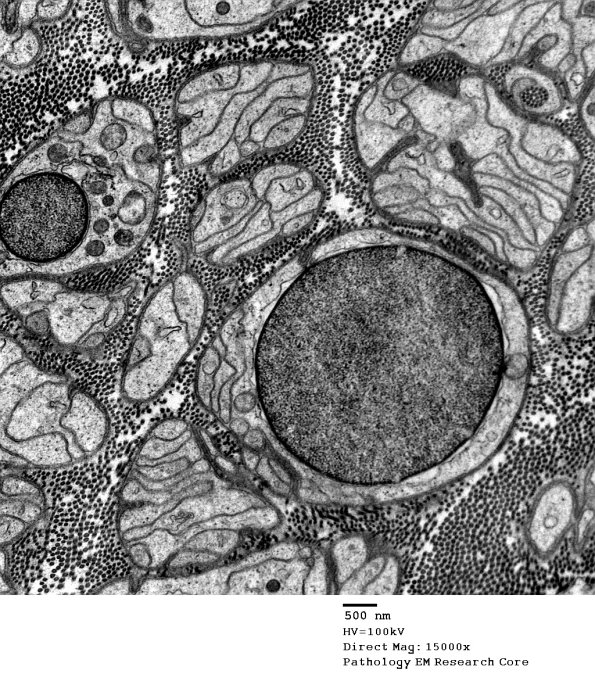

Washington University Experience | PERIPHERAL NEUROPATHY | 4 AXONAL DEGENERATION | 3 Electron Microscopy | 4C2 Axonal Loss, myelinated, near complete (Case 16) EM 034 - Copy

Schwann cell nuclei randomly appear in the bands of Büngner they support.